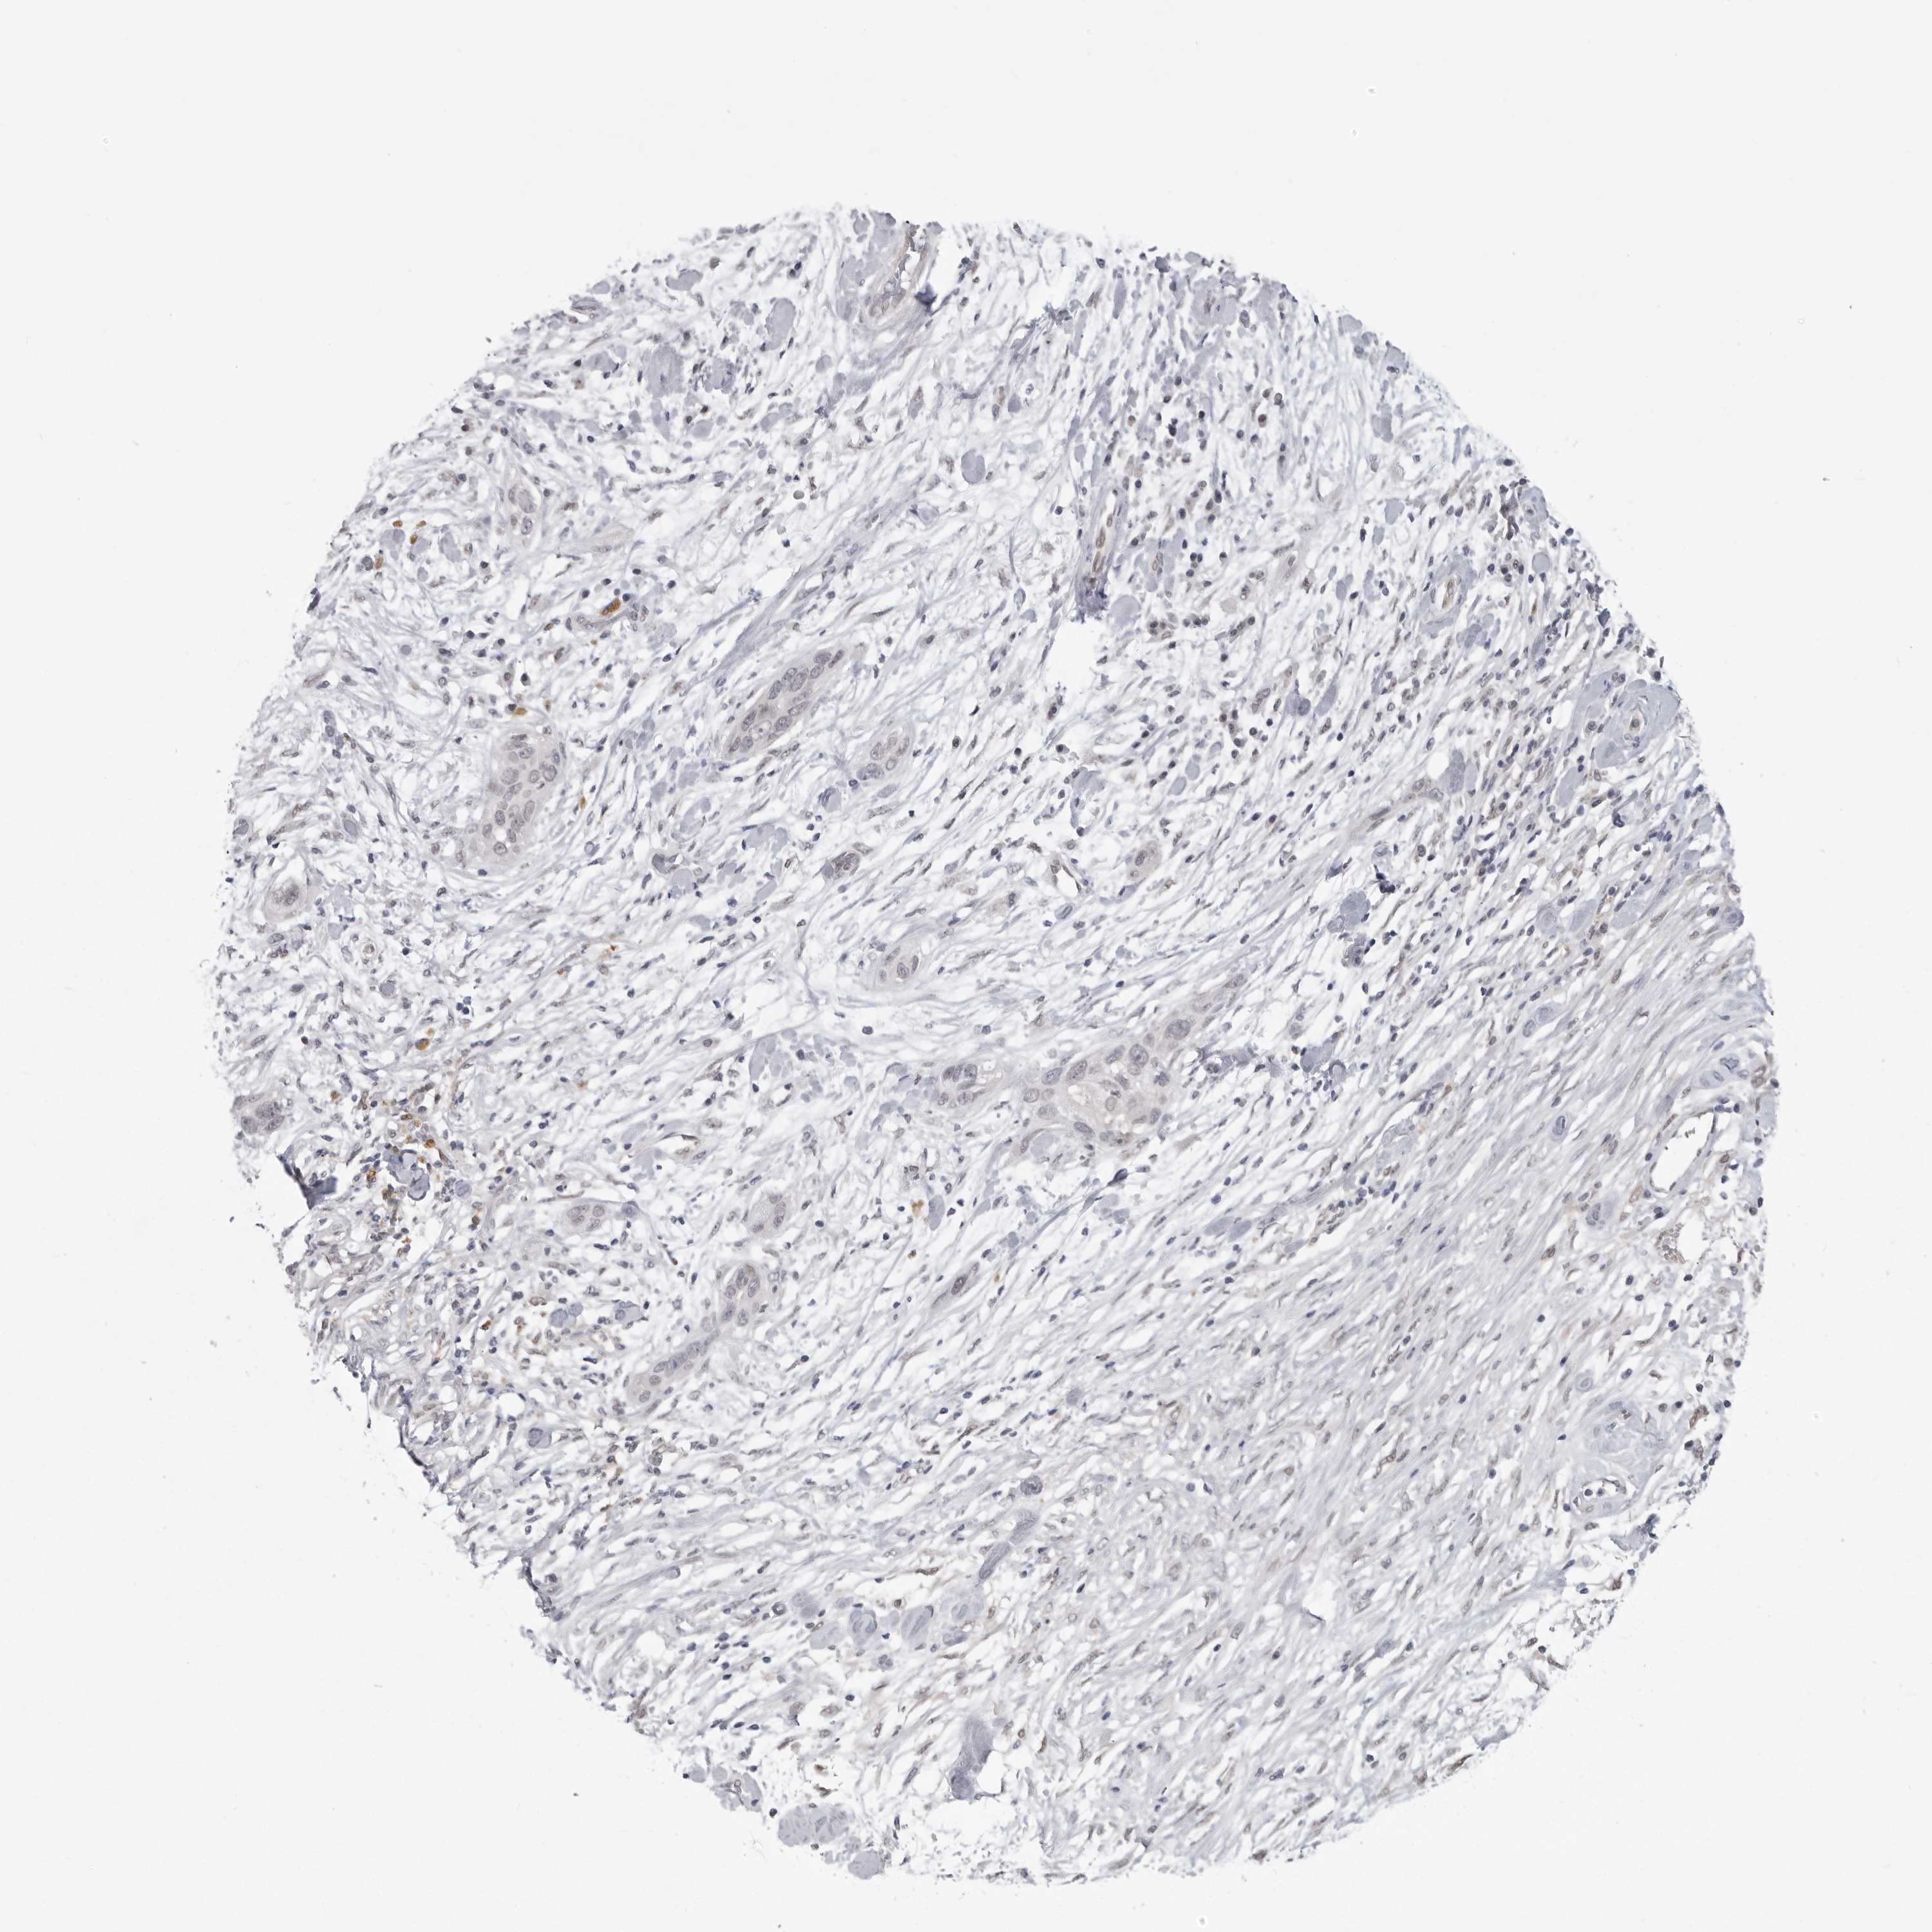

PANCREATIC CANCER - Protein expressioni

A mouse-over function shows sample information and annotation data. Click on an image to view it in a full screen mode. Samples can be filtered based on level of antibody staining by selecting one or several of the following categories: high, medium, low and not detected. The assay and annotation is described here.

Note that samples used for immunohistochemistry by the Human Protein Atlas do not correspond to samples in the TCGA dataset.

Antibody stainingi

Antibody staining in the annotated cell types in the current human tissue is reported as not detected, low, medium, or high, based on conventional immunohistochemistry profiling in selected tissues. This score is based on the combination of the staining intensity and fraction of stained cells.

Each image is clickable and will lead to virtual microscopy that enables deeper exploration of all samples and also displays staining intensity scores, fraction scores and subcellular localization as well as patient and tissue information for each sample.

Antibody HPA023204

Antibody HPA027776

Adenocarcinoma, NOS